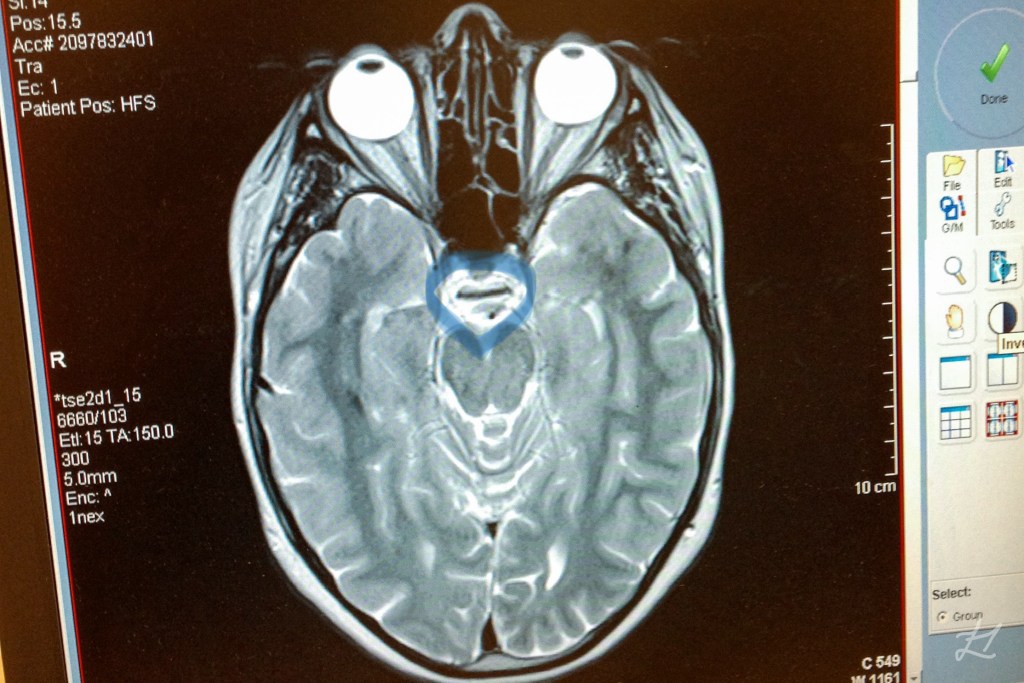

Hi I’m Ren, and the pituitary gland in my brain is purely there for decoration! While that’s a little humour I like to use, living with Panhypopituitarism is a bit more serious.

After my birth, it wasn’t long before I was showing symptoms of my pituitary gland not working. I’m not sure why it never worked, it didn’t have a tumour on it which can be a reason, I just figure the engine didn’t start! 😂

A rare condition where there is deficient production of hormones by the pituitary gland, also known as the ‘master gland’.

For something that is only pea-sized, a working one does a lot. The pituitary monitors and regulates many bodily functions through the hormones that it produces. They are; growth hormone (GH), cortisol hormone (ACTH), thyroid hormone (TSH), reproductive hormones (LH/FSH), melanin hormone (MSH), water hormone (ADH), oxytocin and prolactin.